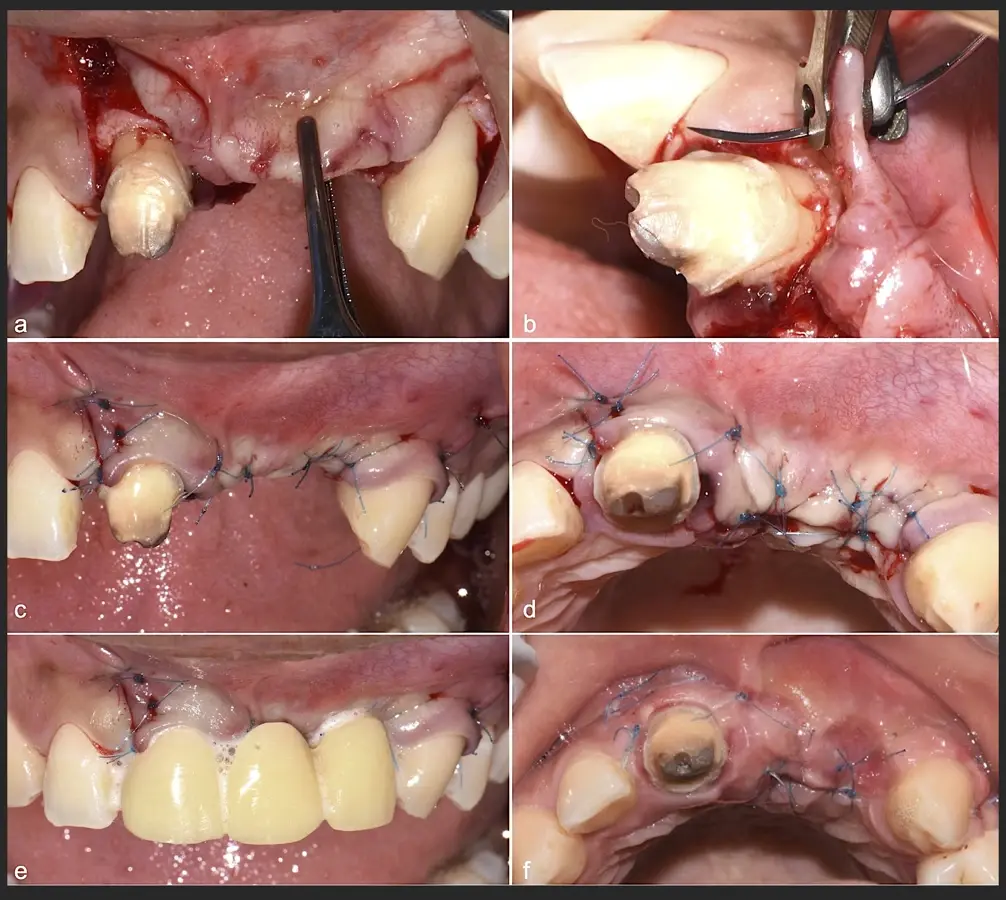

Paciente de sexo femenino de 36 años de edad, llega a la consulta por presentar una restauración protésica inadecuada. En el examen clínico se observa una restauración protésica provisional acrílica sobre las piezas 1.1 y 2.2. Adicionalmente, se aprecia recesión gingival a nivel de la pieza 2.2 y deficiencia horizontal severa de reborde a nivel de la zona edéntula correspondiente a la pieza 2.1. En la evaluación tomográfica se observa ausencia total de tabla ósea vestibular en la pieza 2.2, y se corrobora el déficit en la zona edéntula de la pieza 2.1, para lo cual se indica una reconstrucción de estructuras óseas con hueso en bloque de origen bovino y posteriormente la colocación de implantes dentales.

Figura 40. Secuencia de fijación y modelado del bloque óseo con inserto de corte, eliminación de ángulos agudos (a-d).

Figura 41. Modelado del bloque óseo con inserto plano de punta diamantada (a) para redondear los ángulos agudos y así evitar una dehiscencia o fenestración de los tejidos blandos (b).

Figura 42. El proceso de triturado de biomaterial óseo sustituto en bloque (a - d).

Figura 43. Colocación del biomaterial triturado (a - d).

Figura 44. Pasos para la colocación de la membrana de barrera (a - d).

Figura 45. Afrontamiento de colgajo y sutura (a - e). Control a los 7 días postquirúrgico (f).